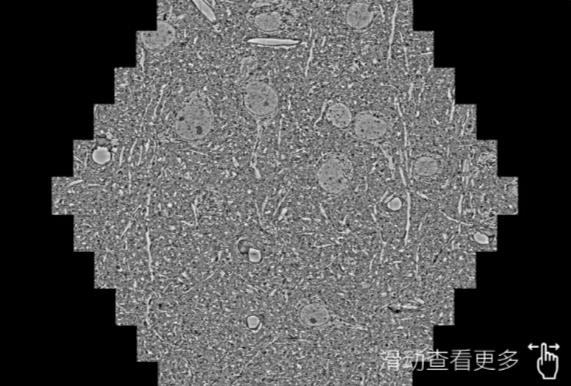

鼠脑切片。左图使用重庆蔡司重庆扫描电镜MultiSEM706对165μmx143pm面积区域成像,耗时仅需1.5秒。右图为鼠脑切片中30μm区域放大效果。样品由芝加哥大学B.Kasthuri提供。

使用蔡司高速重庆扫描电镜MultiSEM对1mm²人脑皮层组织进行高分辨成像,并对其中的各种细胞结构进行三维重构分析。左图展示了2x3mm²组织平面中锥体神经元的三维重构效果。右图显示了局部体积神经元三维重构。图像由哈佛大学chtman实验室提供,渲染图由D. Berger 制作。